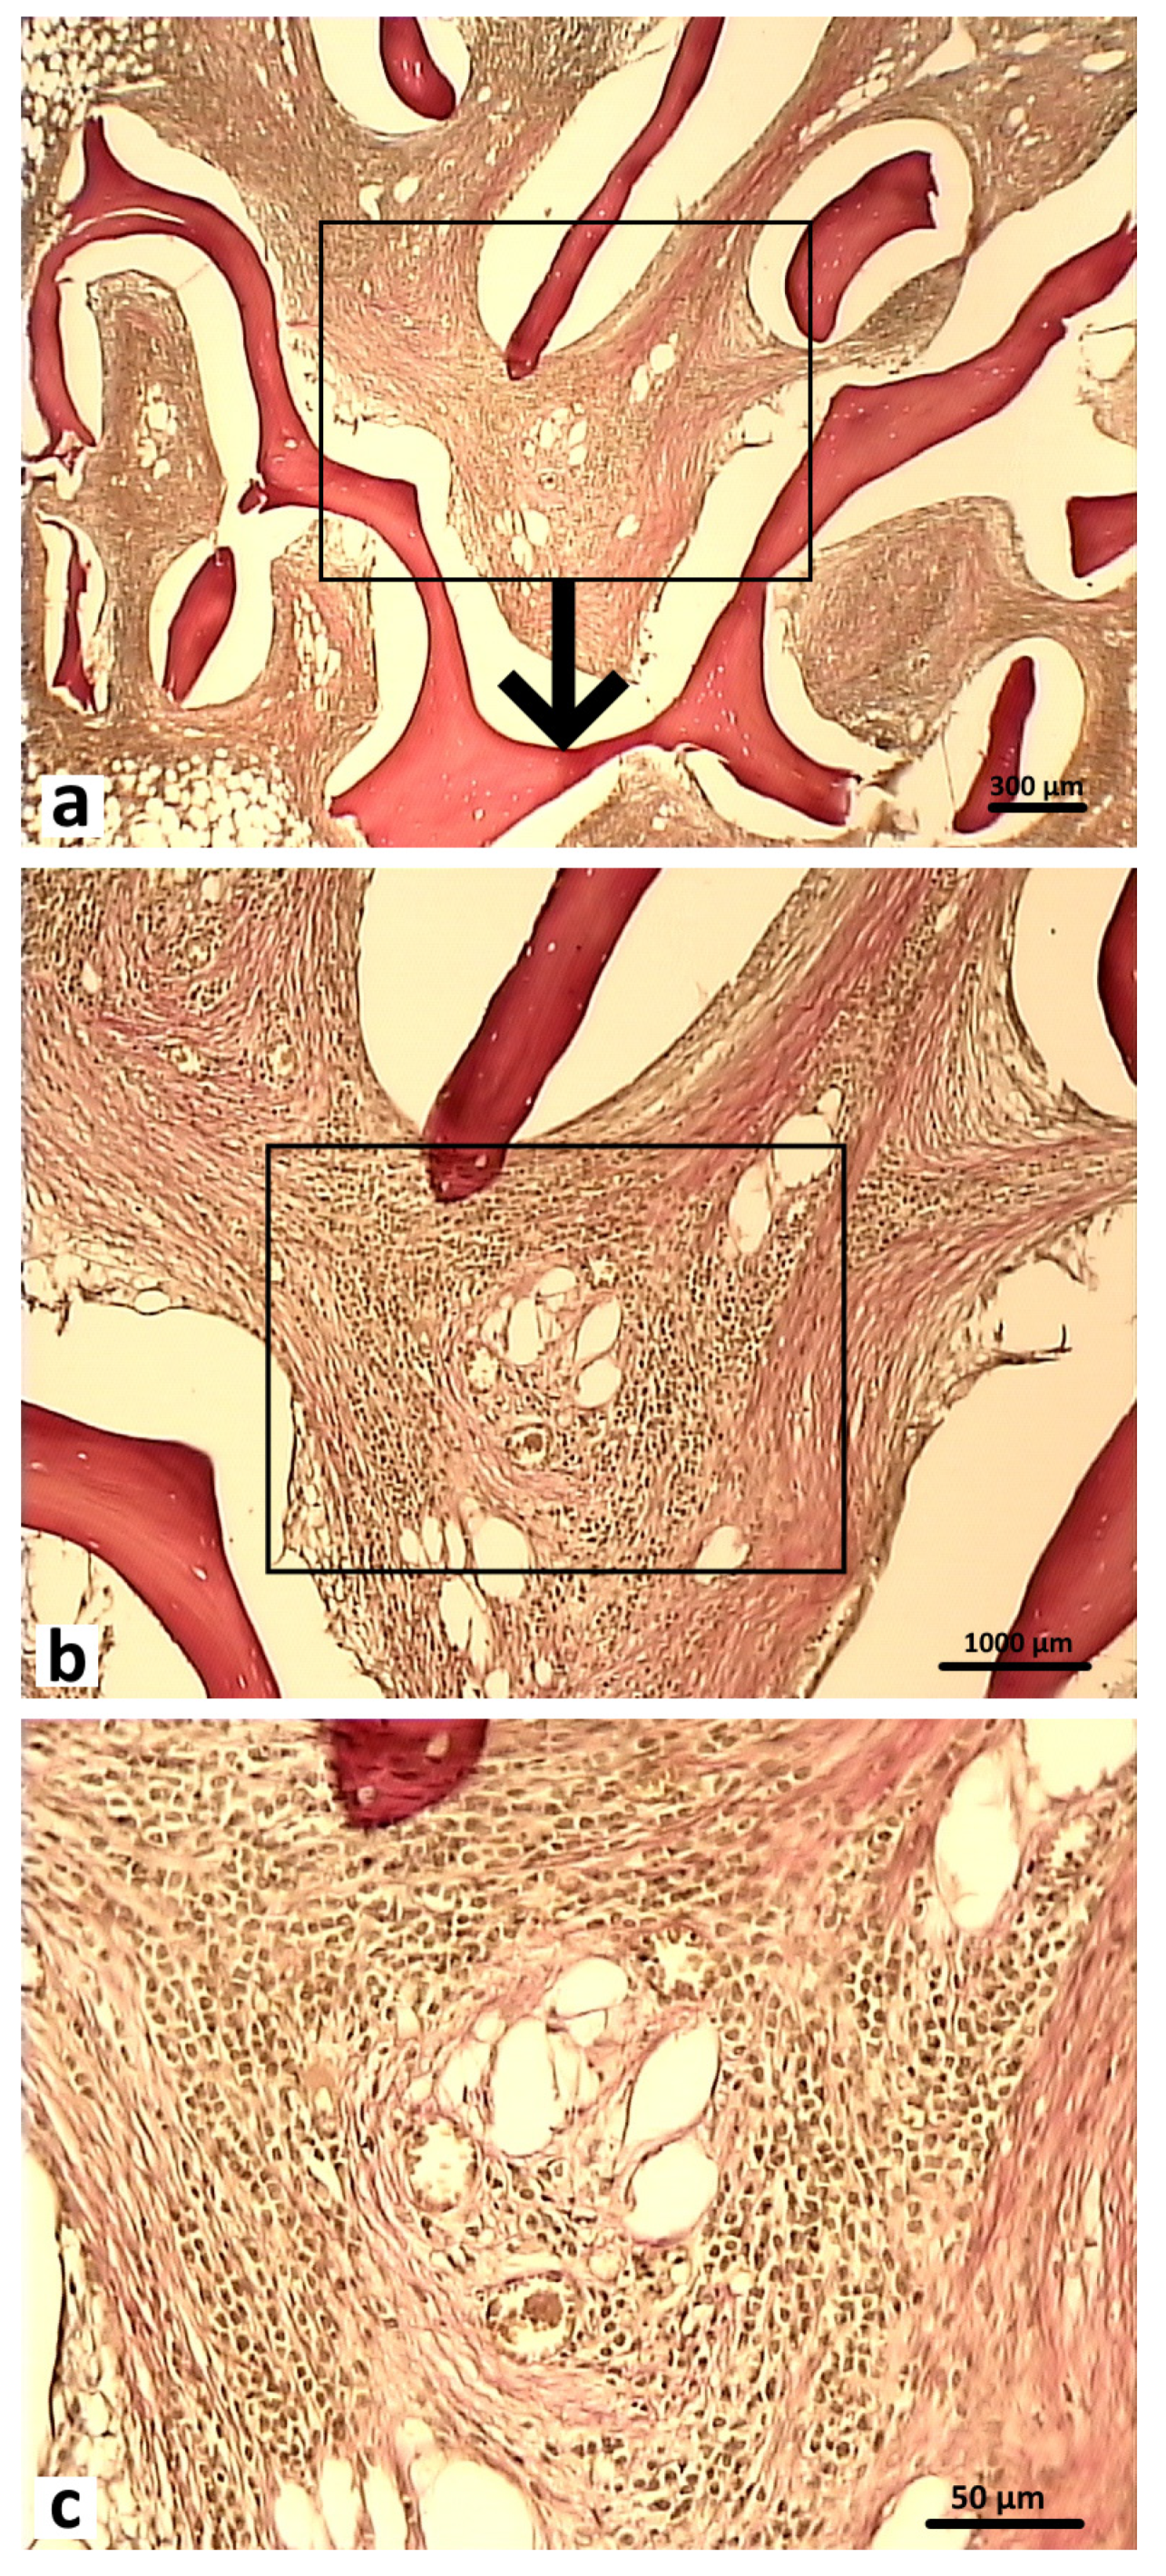

After 2 months of the postoperative period, differences were noted in the signs of reparative regeneration in the graft localization area between the control and experimental group animals. The process of integration of the control material into the surrounding tissues was more intensive. These sections showed structural elements of the osteoplastic matrix, surrounded by a heterogeneous cell-fiber population of fibroreticular tissue and functionally active microvessels (Figure 12).

Figure 12.

Graft localization area in the control group animals 2 months after surgery. Structural elements of the osteoplastic matrix surrounded by the heterogeneous cell-fiber population of the fibroreticular tissue. Functionally active microvessels (indicated by arrows), Van Gieson staining: (a) 40×; (b) 200×; (c) 400×.

After 2 months of the postoperative period, the sections of bone tissue in the experimental group animals demonstrated poorly differentiated groups of cells and connective tissue fibers, and single microvessels in the graft localization area (Figure 13).

Figure 13.

Graft localization area (hybrid polymer) in animals in the experimental group, 2 months after surgery: 1—experimental material; 2—poorly differentiated cells; 3—connective tissue fibers. Van Gieson staining; 400×.

Newly formed bone tissue was found in the area of graft contact with the bone marrow and in the bone defect area in the animals in the experimental group (Figure 14). At 2 months after surgery, the foci of chondroid differentiation in the perifocal area remained in both the control and experimental group animals.

Figure 14.

Graft localization area (hybrid polymer) in animals in the experimental group, 2 months after surgery (1—newly formed bone tissue, 2—bone marrow, 3—implant zone. The area of the bone defect is indicated by a curly bracket). Hematoxylin and eosin staining: (a) 40×; (b) 200×.